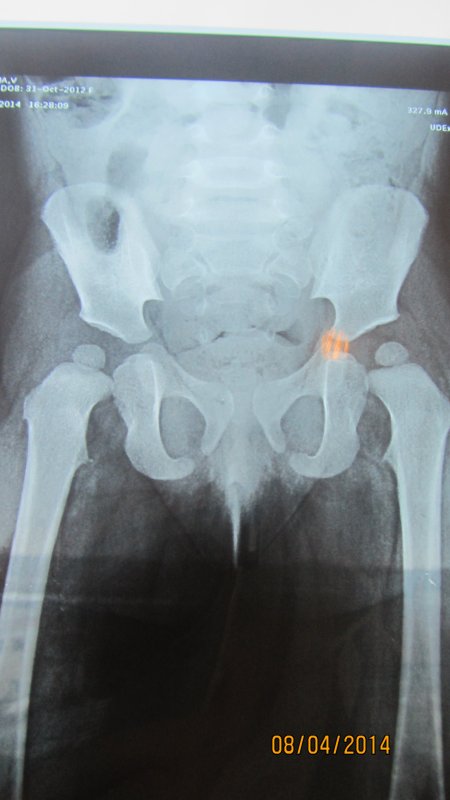

Константин Сергеевич, доброе время суток!!! Очень нужна Ваша консультация!!! Мы просто в отчаянии. Помогите, пожалуйста! Нашей дочки сейчас 1 год и 5 месяцев. В 3 месяца сделали узи т/б суставов- заключение оба сустава-тип Iа. В 6 месяцев пошли на прием к ортопеду: ограничений отведения нет; кожные ягод. и подкол. складки симметр.; длина ног Д=S; ось нижних конечностей правильная, тенденция к вальгусной деформ. стоп.; объем движений в Ш.О.П. полный DS: плосковальгусные стопы. Назначили ЛФК, орторежим, ортообувь с фикс. ГСС. явка в 1 год Мы пришли в 9 месяцев. Нам написали все тоже самое, только добавили мяч и коврик. Явка через пол года. У нас же с 6 месяцев в т/б суставах часто был слышен хруст (щелчек), когда я меняла памперс , однако массажист говорил, что ничего не хрустит (массаж мы делали 5 раз)(массажист у нас врач-хирург) На этом дело и было бы закончено НО!! Хруст все же продолжался. Мы сделали узи т/б суставов в 1,1месяц в НИИТО заключение: признаки задержки темпов оссификации ядер, оба сустава- тип 1а. Затем отправились на консультацию к ортопеду в НИИТО. назначили: ЛФК, массаж, орто обувь, электрофорез, парафин, плавание, Д3 в возростной дозировке, ходьба по коврику, мультитабс малыш кальций 1/4 т. творог, мясо и ренгенография т/б в прямой проекции через 3 месяца. Сходили еще к одному ортопеду, нам сказали ренген делать не обязательно у вас нет дисплазии. Однако мы всеже сделали ренген в НИИТО в 1,5 месяцев и результат по нему такой:- ядра окостенения головок бедренных костей расположены в проекции ацетабулярной впадины, симметричны, децентрированы; - ацетабулярный угол D=28 S=25; -проекционный ШДУ D=156 S=143; - угол наклона плоскости входа во впадину D=37 S=39; - угол Виберга D= 7 S=11; - линии Шентона изломана слева, линии Кальве не нарушены; - симптом Омбреданна отрицательный с обеих сторон. Заключение: Двусторонняя дисплазия тазобедренных сочленений. Помогите, пожалуйста! Что нам делать? Как к Вам можно попасть на прием?? Очень хочется услышать Ваше мнение!

Здравствуйте. Да, дисплазия есть. По тактике лечения - ответил в ЛС. |

нет, рентгенограмма удовлетворительного качества, ошибки нет. Неправильная укладка всегда заметна на снимках. Да, ребенок уложен неидеально, но качество снимка не сильно пострадало, для постановки диагноза достаточно.

Шину носить в течение 6 мес, снимать можно на купание, массаж (хотя, строго говоря, массажу она не мешает), физиопроцедуры. Остальное время она должна надета. Шина центрирует головки бедренных костей в суставных впадинах, при ее ношении происходит правильное формирование тазобедренного сустава, при этом шина не ограничивает движений в коленных суставах и совсем немного-в тазобедренных. Ношение шины - только на голенях, на нижних их третях (не на бедрах!). |